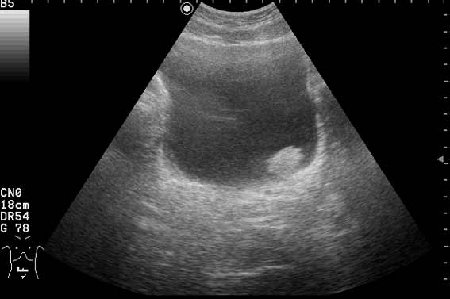

Находка у мужчины 65 лет

Ну конечно же, на представленных эхограммах - папиллярная опухоль мочевого пузыря.

Писать в заключении, что это полип - нельзя, это случай при котором руководствуются правилом - считаем опухоль злокачественной, пока не доказано обратное. Опухоль расположена над устьем левого мочеточника, нет обструкции устья и терминального отдела мочеточника (доказательство - наличие полноценного выброса мочи из устья) - что, в свою очередь, говорит против интралюминальной уретеральной опухоли.